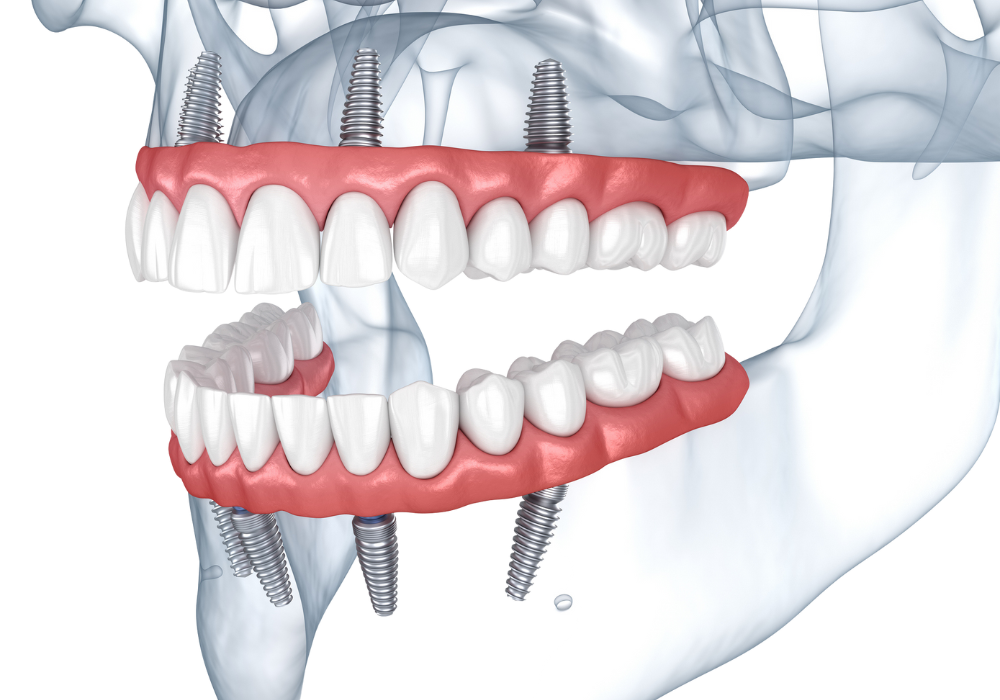

La prothèse fixe sur implants

Une série d’implants est placée dans la mâchoire pour supporter un bridge complet fixé de manière permanente.

Cette solution offre un confort maximal : les dents sont solidement ancrées, ne bougent pas et permettent une mastication naturelle.

Un examen clinique et radiologique (scanner, empreintes numériques…) permet d’évaluer la qualité osseuse et de déterminer le nombre d’implants nécessaires.Pose des implants

Réalisée sous anesthésie locale dans des conditions stériles. Cette étape est bien tolérée et indolore (réalisée sous anesthésie locale).Phase d’intégration

Les implants se soudent naturellement à l’os de la mâchoire (ostéointégration), assurant la stabilité de la future prothèse.Mise en place de la prothèse définitive